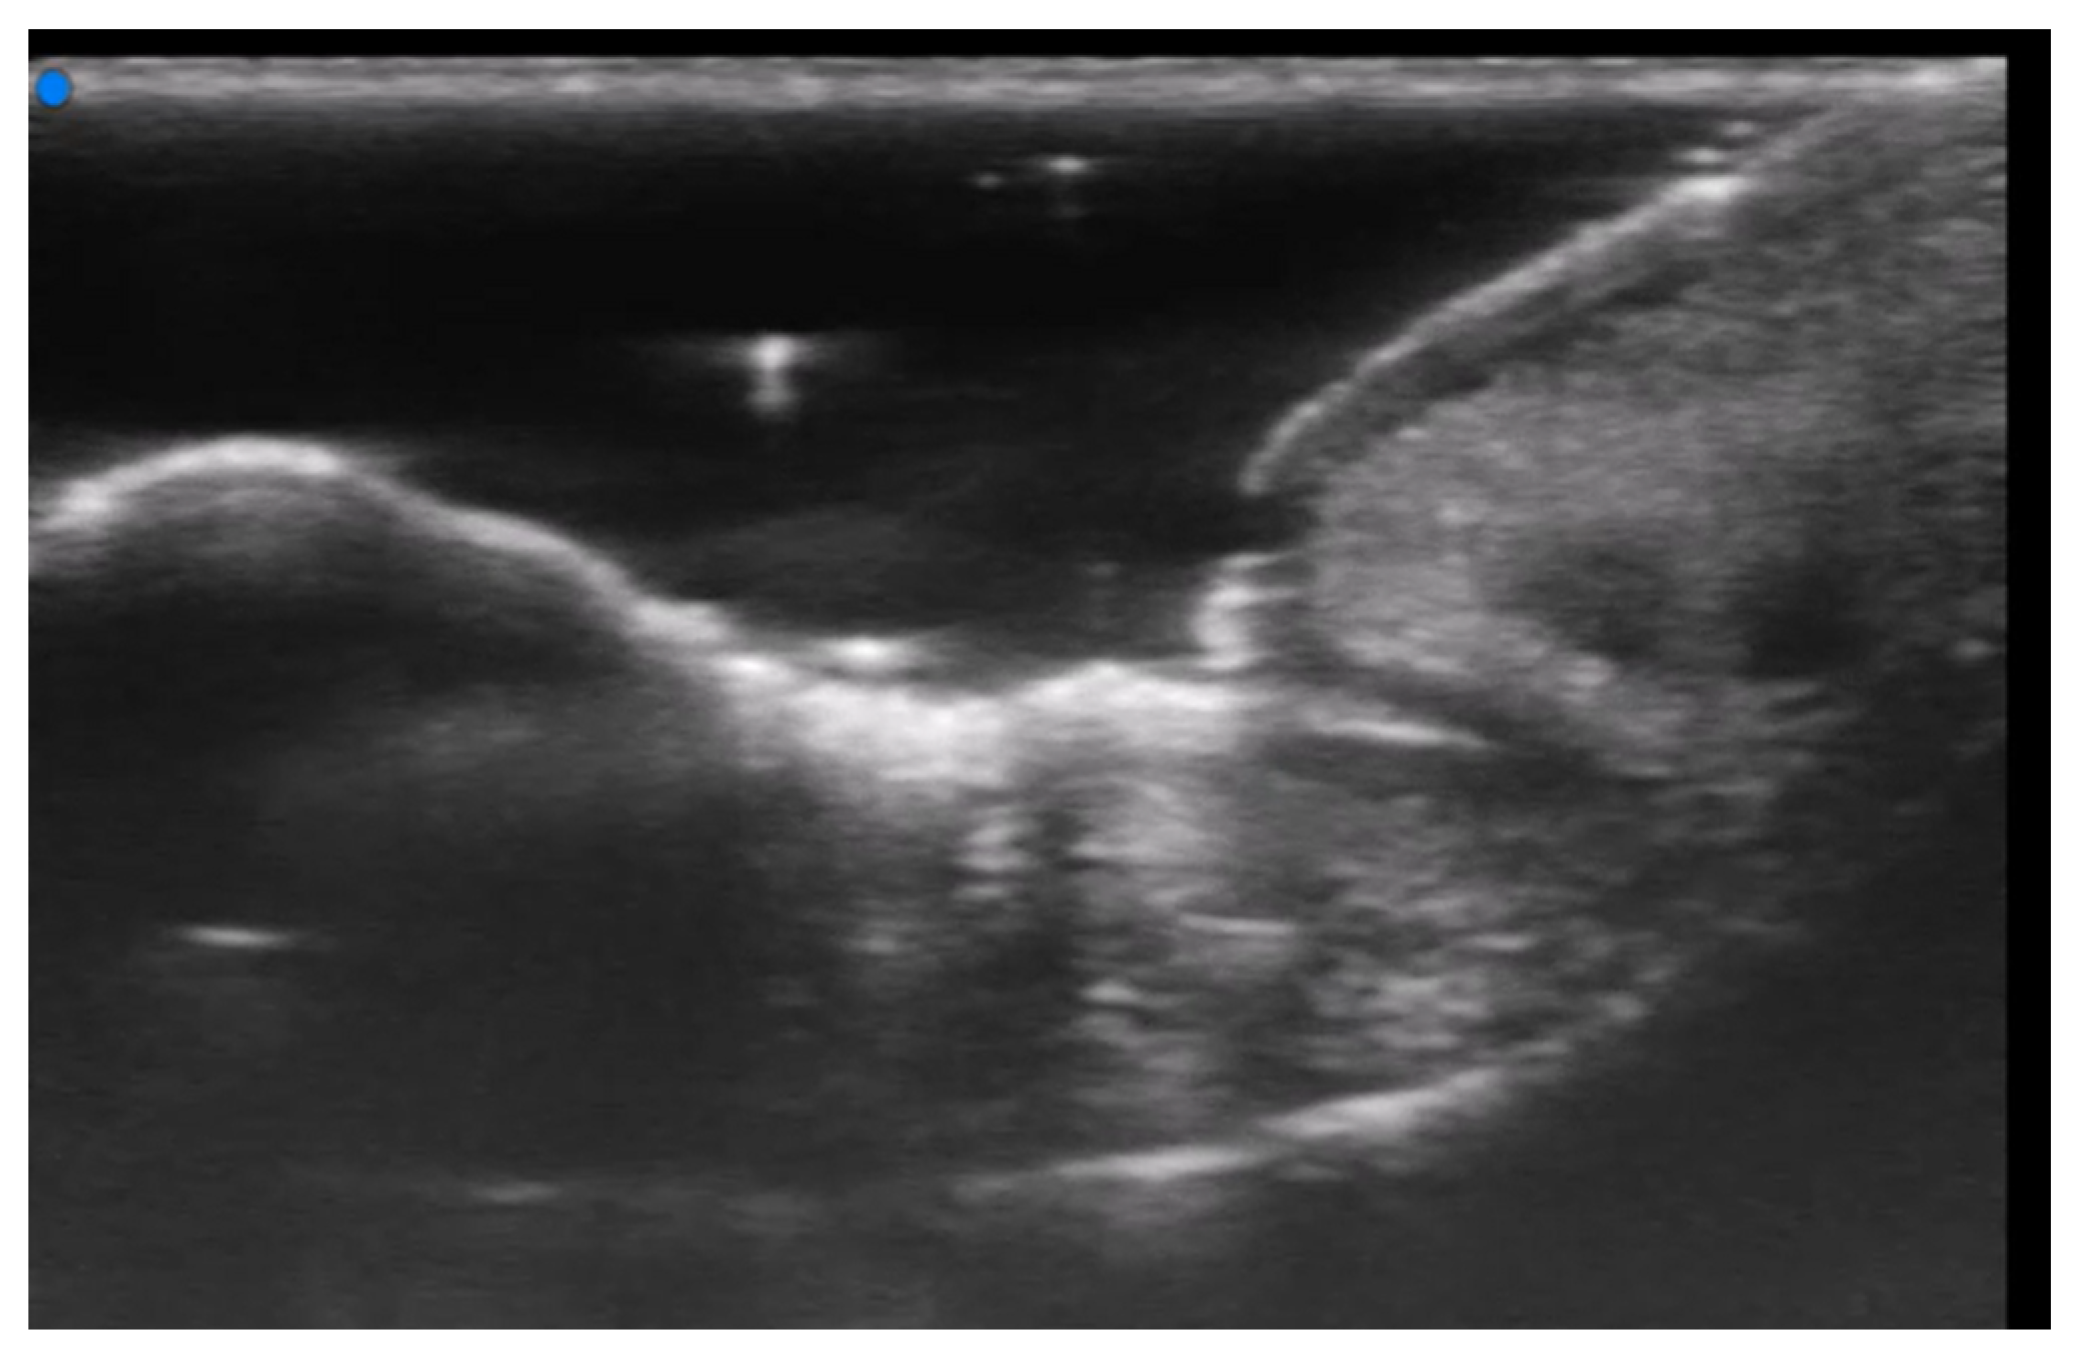

- Del Vecchio, D.; Kenkel, J.M. Practice Advisory on Gluteal Fat Grafting. Aesthetic Surg. J. 2022, 42, 1019–1029. [Google Scholar] [CrossRef]

- Vidal-Laureano, N.; Huerta, C.T.; Perez, E.A.; Earle, S.A. Augmented Safety Profile of Ultrasound-Guided Gluteal Fat Transfer: Retrospective Study with 1815 Patients. Aesthetic Surg. J. 2024, 44, NP263–NP270. [Google Scholar] [CrossRef] [PubMed]

- Elsaftawy, A.; Ostrowski, P.; Bonczar, M.; Stolarski, M.; Gabryszuk, K.; Bonczar, T. Buttock Augmentation with Ultrasonic Liposuction and Ultrasound-Guided Fat Grafting: A Retrospective Analysis Based on 185 Patients. J. Clin. Med. 2024, 13, 1526. [Google Scholar] [CrossRef]

- Elsaftawy, A.; Ostrowski, P.; Bonczar, M.; Stolarski, M.; Gabryszuk, K.; Bonczar, T. Enhancing Buttock Contours: A Safer Approach to Gluteal Augmentation with Ultrasonic Liposuction, Submuscular Implants, and Ultrasound-Guided Fat Grafting. J. Clin. Med. 2024, 13, 2856. [Google Scholar] [CrossRef]

- Wang, B.; He, P.; Zhao, R. B-ultrasound-assisted gluteal fat grafting in Asians: A prospective study of quantitative results from three-dimensional imaging and B-ultrasound analysis. J. Plast. Reconstr. Aesthetic Surg. 2024, 94, 12–19. [Google Scholar] [CrossRef] [PubMed]